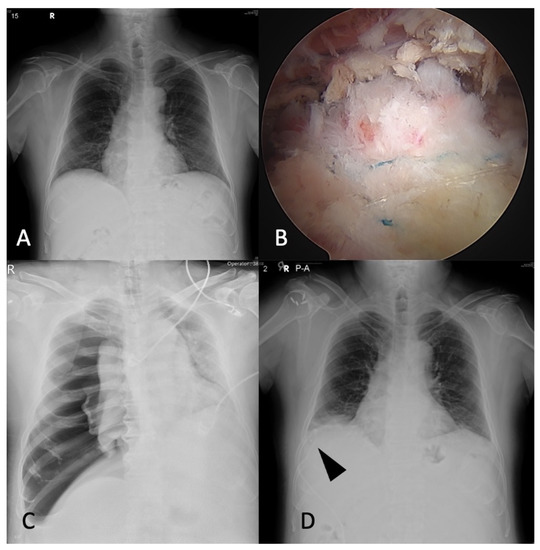

2.2. Case 2